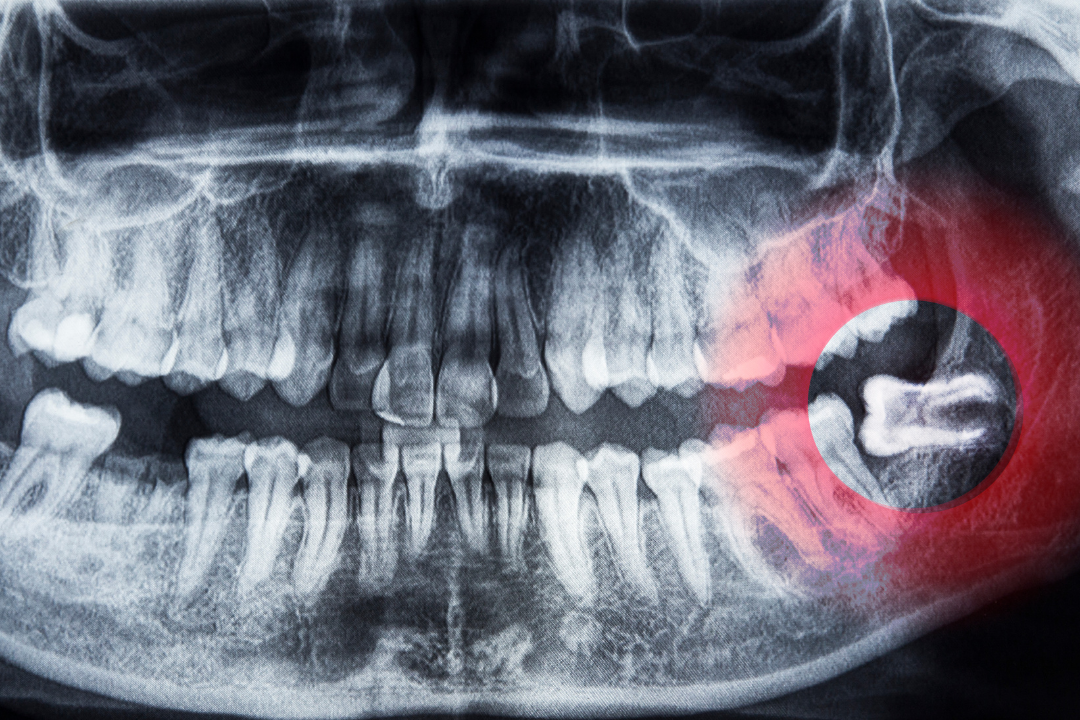

1. Wisdom Tooth Removal

The third molars, commonly known as wisdom teeth, often don’t have enough room to erupt properly. This can lead to crowding, infections, or pain. Our oral surgeons safely remove impacted or partially erupted wisdom teeth, preventing complications and ensuring a smooth recovery.